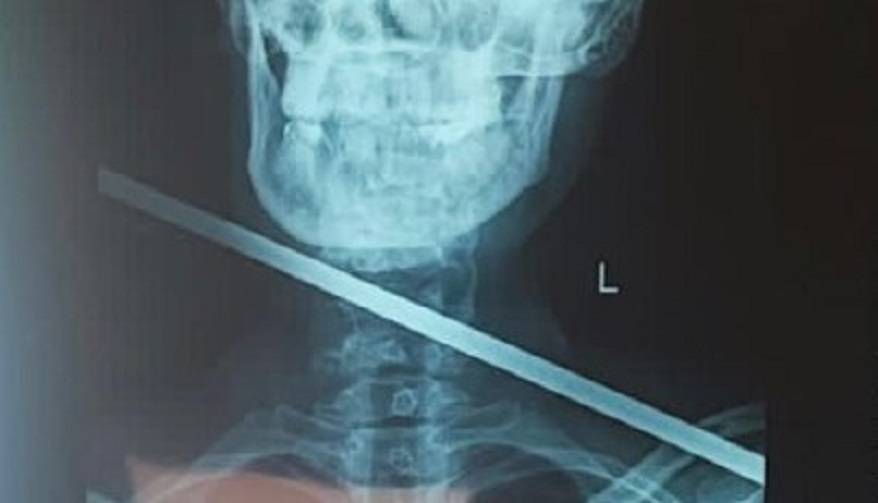

В тг-канале Минздрава отмечают, в «тысячекоечную» больницу обратилась пациентка с гарпуном в шее, при этом пострадавшая сохраняла спокойствие. По мнению врачей, такое ранение считается смертельным, в этом случае стрела не задела жизненно важные органы.

Врач добавил, что под общей анестезией была проведена ревизия раны, частично была повреждена щитовидная железа, после удаления инородного тела, железу удалось сохранить.

Операция длилась полтора часа и прошла успешно с минимальной кровопотерей.